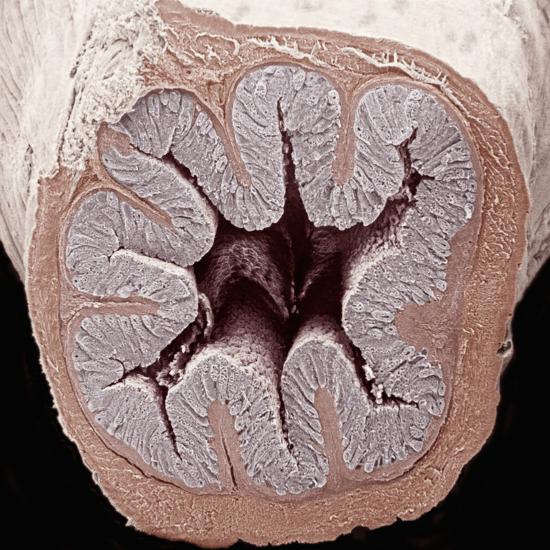

'Cross-Section of the Mammal Colon or Large Intestine from the Lumen Outward are the Mucosa ...

The lumen, is simply the middle of an artery, blood vessel or capillary, it is the space that the blood flows through.